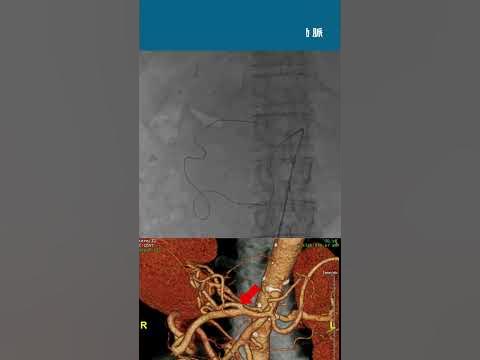

胃十二指腸動脈は消化性潰瘍疾患の合併症として発生することのある重大な胃腸出血の原因となる可能性がある。十二指腸の第二部の後内側壁との密接な関係により、十二指腸の深く入り込んだ潰瘍や腫瘍が胃十二指腸の「出血の動脈」から激しい出血を引き起こす場合がある。とりわけ、この領域の大量の動脈網により血管内の高い流量が確保されているからでもある。

補足画像